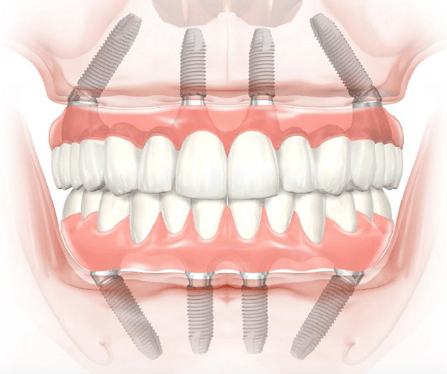

All-on-4, cunoscuta si sub denumirea Fast & Fixed, este o procedura chirurgicala de reabilitare totala.

Conceptul de tratament All-on-4/6 este o procedură chirurgicala si protetică (adică înlocuirea dinților lipsă) care asigură o înlocuire permanentă a acestora.

Adesea, pierderea dinților este însoțită de pierderea osului maxilar, ceea ce pune problema reconstrucției osului maxilar care necesită grefarea osoasă . Tehnica All-on-4 profită de osul dens care rămâne în partea din față a maxilarelor și prin plasarea celor două implanturi posterioare în unghi pentru a evita sinusul – cavități în maxilarul superior – și a canalul mandibular în maxilarul inferior -;

In cazul inserarii a 4 implanturi se pot realiza lucrari protetice definitive cu dinți din rășină acrilică (sau alte materiale cu greutate redusa) peste o bara de titan.

In cazul in care oferta osoasa este suficienta pe zonele laterale, se pot insera 6 implanturi si se pot realiza lucrari protetice definitive mai estetice si cu fiabilitate mai mare (metalo – ceramica sau zirconiu);• In ce consta aceasta procedura?

– inserarea a 4 sau 6 (sau 8 in unele cazuri) implanturi/arcada – in functie de lucrarea protetica pe care si-o doreste pacientul.